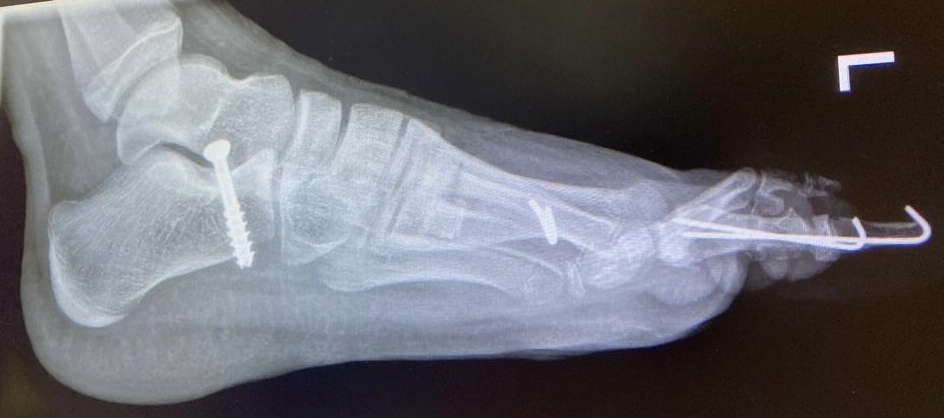

Calcaneus-Osteotomie

Die minimalinvasive Calcaneusverschiebeosteotomie bietet eindeutige Vorteile gegenüber dem offenen Verfahren, sodass wir bei Kindern und Jugendlichen nahezu keine offene Verschiebeosteotomie mehr durchführen. Am Calcaneus liegt die offene Wachstumsfuge dorsal. Bei der Durchführung müssen Schenkel der V-förmigen Osteotomie daher etwas steiler angelegt werden, in einem stumpfen Winkel (siehe Abb. 3 a-j). Für die Osteotomie liegen unsere Patienten auf dem Rücken und der BV wird für die exakte Seitaufnahme eingestellt. Der Fuß lagert auf einem hohen OP-Kissen und die Osteotomie kann bequem mit einem langen Kirschner-Draht und einem sterilen Stift angezeichnet werden (Abb. 15).

Damit lässt sich im Verlauf Röntgenstrahlung für die jungen Patienten vermeiden und die minimalinvasive Osteotomie kann sicher durchgeführt werden. Anschließend erfolgt die Verschiebung oder Impaktion. Ist ein Gleiten nach plantar oder cranial des distalen Fragmentes erwünscht, wird die Osteotomie schräg ohne V-Form entweder verlängernd oder verkürzend durchgeführt (Abb. 16).

Durch den knöchernen Defekt der Fräse gelingt die Verschiebung bei der minimalinvasiven Osteotomie im Fall von strukturell festen Klumpfüßen mit starkem Zug der verkürzten Achillessehne oder bei einer fixierenden spastischen Grunderkrankung einfacher gegenüber dem offen Verfahren. Ein weiteres Plus bei hyperaktiven Weichteilen ist die Vermeidung der ungewollten Cranialisierung des dorsalen Fragmentes durch die V-förmige Osteotomie (Abb. 16).

Die minimalinvasive Calcaneusverschiebeosoteotomie kommt somit in der Versorgung von kindlichen und jugendlichen Fußdeformitäten in einem weiten Erkrankungsspektrum zum Einsatz (Abb. 16):

- Plattfuß – Varisation

- Klumpfuß residual – Valgisation und ggfs. Cranialisation sowie Impaktion

- Klumpfuß überkorrigiert – Varisation und ggfs. Plantarisierung

- Hohlfuß – Cranialisation und ggf. Valgisation (alternativ minimalinvasive Austin-Osteotomie)